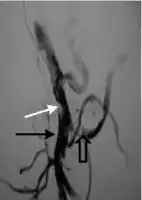

.png.webp)

Portal vein thrombosis affects the hepatic portal vein, which can lead to portal hypertension and reduction of the blood supply to the liver.[5] It usually happens in the setting of another disease such as pancreatitis, cirrhosis, diverticulitis or cholangiocarcinoma.[6]